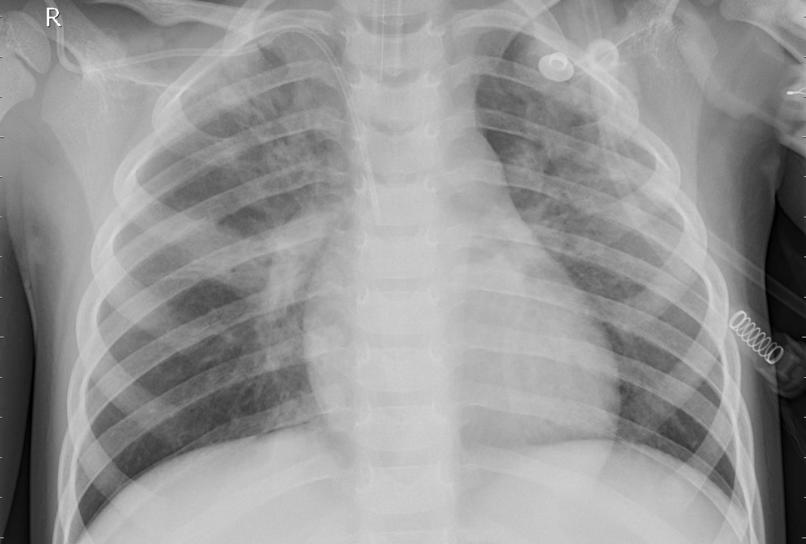

1. Data Collection We collected a diverse dataset of chest X-ray scans from various sources, ensuring it included both normal and pneumonia cases. This data was crucial for training and testing our models.

2. Data Preprocessing We cleaned and preprocessed the images, resizing them, normalizing pixel values, and creating labels to distinguish between normal and pneumonia cases.

3. Model Development We implemented CNN architectures, fine-tuning them to optimize the detection of pneumonia features in X-ray scans. We utilized transfer learning, using pre-trained models as a starting point.

5. Deployment The trained model was integrated into a user-friendly application that allowed healthcare professionals to upload X-ray scans for real-time analysis. The system provides a prediction of whether pneumonia is present or not.